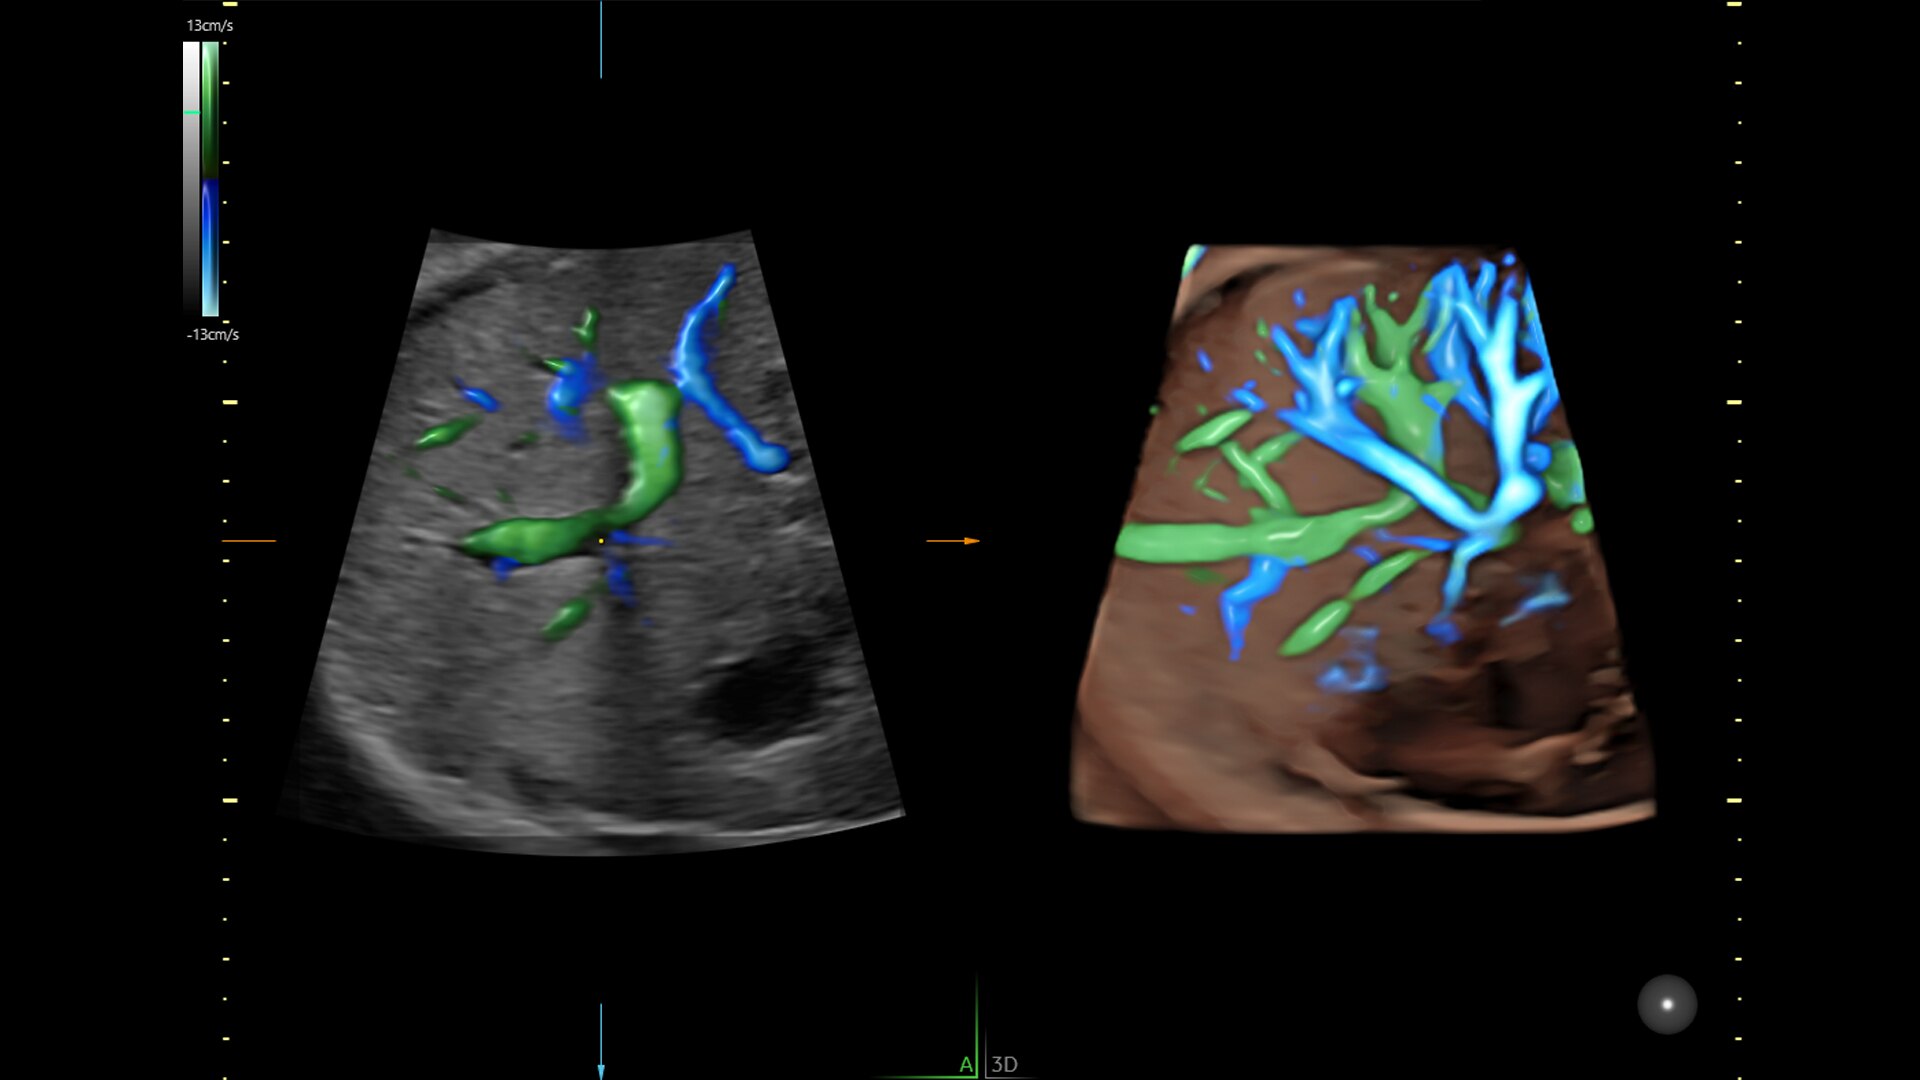

Fast, easy 3D-like blood flow visualization

Next level color Doppler that delivers exceptional sensitivity for easy, fast visualization of blood flow, displaying a 3D like appearance as seen in this 27-week fetal heart.

2-radiantflow-image